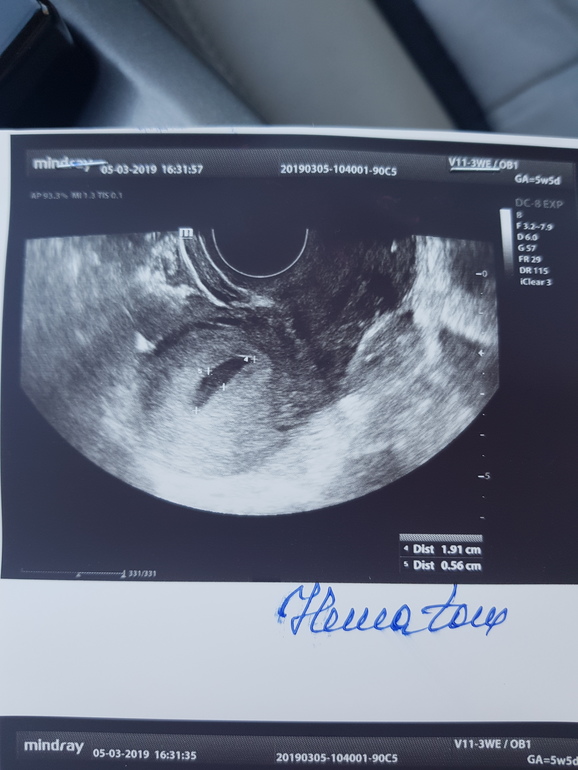

Вчера была на узи, чтобы исключить внематочную. Нашли плодное яйцо 4,3 мм и большую гематому рядом 19,1 на 5,6 мм. И еще кисту желтого тела 5 см.

Посмотрите,пожалуйста узи,кто разбирается. Поначиталась гематома это отслойка, но у меня она отдельно от яйца.. не похоже на отслойку. С дочкой все было идеально, ни разу никаких проблем не было..

Вот фото узи

Гематома отдельно